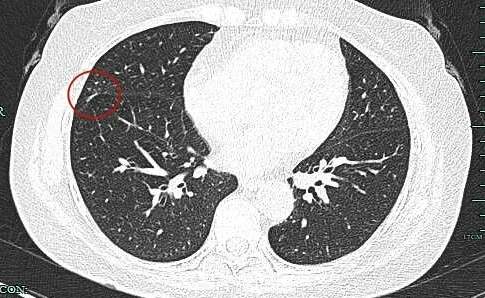

影像展示与分析:

病灶出现,磨玻璃密度,轮廓较清,此层示见显著实性成分。

边缘不平有毛刺,实性成分开始出现,外周仍是磨玻璃密度的。血管与之关系密切。

典型毛刺征,磨玻璃部分瘤肺边界清,表面不平,灶内密度不均。

实性成分占比高,表面不平,有细毛刺征,整体感觉有一定收缩力。

病灶大部分实性,边缘细毛刺与少许磨玻璃成分。

感觉整体病灶有膨胀性,边缘有毛刺征,灶内密度不是太致密。

叶间胸膜受牵拉凹陷,有微小血管进入,表面毛刺与不平。

实性成分也有明显毛刺,叶间裂牵拉明显,表面有分叶征。

边缘紧贴叶间裂,密度较高。

病灶没有钙化,是软组织密度影。